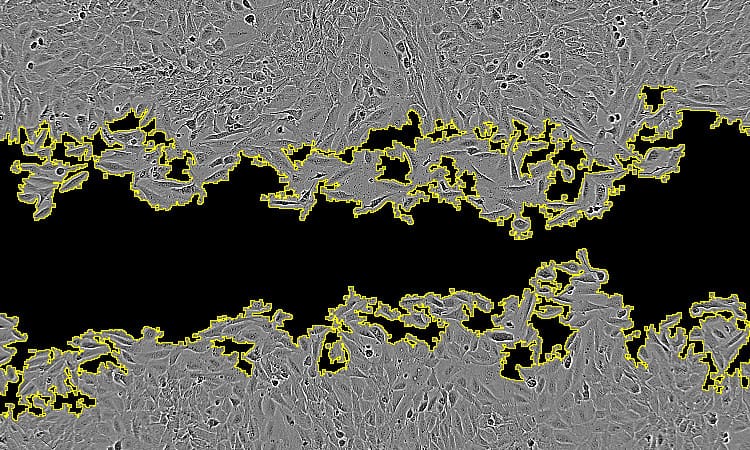

Macrophages are immune cells that are found in the intestine and, although named for their ability to engulf and digest cellular debris, microbes, and other foreign substances, they also have important inflammatory and anti-inflammatory roles. Tomas Castro-Dopico, a researcher in Menna’s group, studied gut biopsies from patients with IBD, as well as lab models of IBD, to study the signalling molecules (known as cytokines) sent between immune cells to amplify or suppress inflammation in the gut.

Tom, other members of Menna’s group, and collaborators at the Cambridge Institute of Therapeutic Immunology and Infectious Disease and the Wellcome Sanger Institute, identified a major cytokine that calibrates wound healing and bacterial defence functions of macrophages in the intestine, GM-CSF (granulocyte macrophage colony stimulating factor). They also identified the main cellular source of GM-CSF: innate lymphoid cells. The team found that lower amounts of GM-CSF promoted wound healing by macrophages, while higher levels increased inflammation, inhibited wound healing, and made macrophages that are better at dealing with gut-invading bacteria.